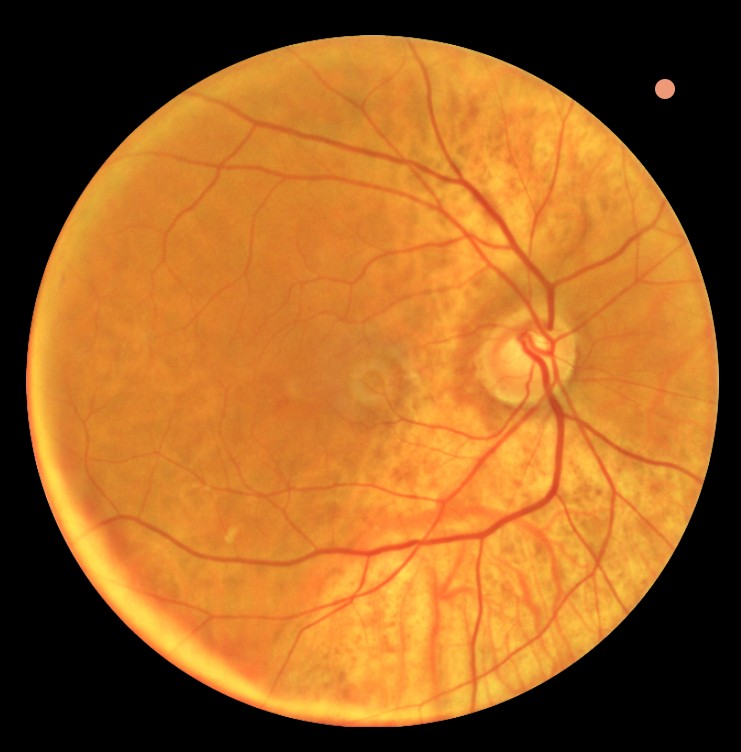

- Controle bij maculadegeneratie of diabetische retinopathie

Diabetes kan een belangrijke reden zijn voor een vervolgonderzoek, aangezien deze aandoening directe invloed kan hebben op de ooggezondheid. Regelmatige controles zijn essentieel om schade aan het netvlies vroegtijdig te signaleren en verdere achteruitgang te voorkomen.

Afhankelijk van de indicatie kunnen aanvullende onderzoeken worden uitgevoerd, zoals een gezichtsveldmeting, OCT-scan van de oogzenuw, of uitgebreide beoordeling van het netvlies met pupilverwijdende druppels.